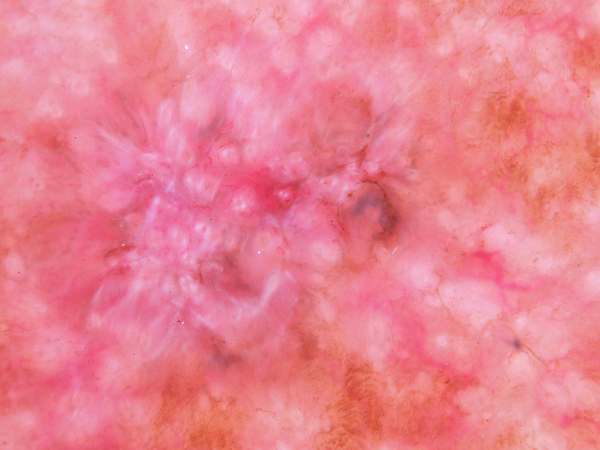

Actinic keratoses